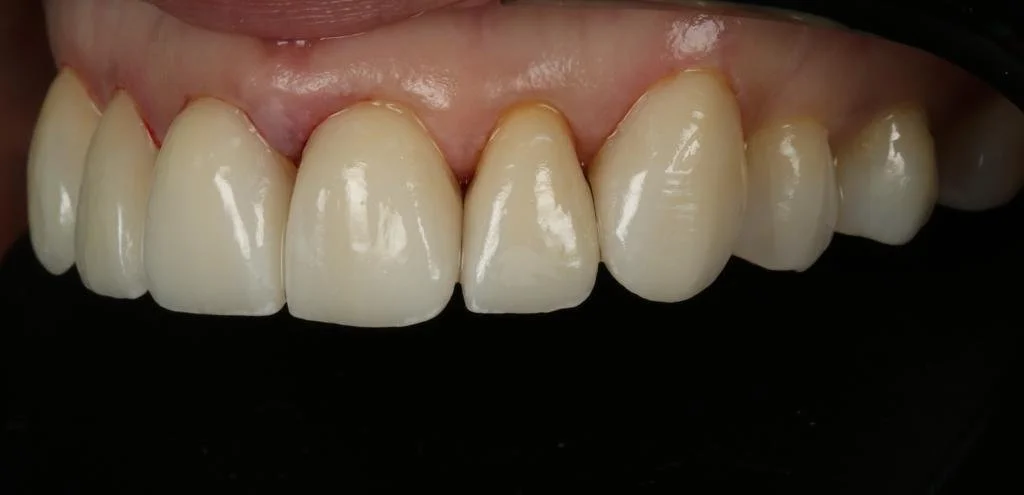

Cerec Reshape and Stain Graze